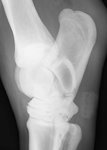

• Lateromedial radiographic projection of the right hock of a mature horse showing osteophyte formation and narrowing of the distal intertarsal joint

• Oblique radiographic projection of the same hock showing marked osseous reaction and narrowing of the distal intertarsal joint

Hindlimb lameness is a common occurrence in equids of all shapes, sizes and athletic disciplines. Not only does it have welfare implications for the horse, it is also a performance limiting factor and a source of economic loss. Once identified it may present a diagnostic challenge to veterinary surgeons when trying to pinpoint the source of pain. There are a multitude of orthopaedic conditions affecting the equine hindlimb, which may affect any soft tissue or bony structure from the distal phalanx to the pelvis. This article focuses on osteoarthritis of the small hock joints as one of the more common causes of hindlimb lameness.

Radiographic examination of the tarsus may be conducted, generally four views are required as in some cases lesions may only be present in one radiographic view. Images of both hocks should be obtained as disease is often bilateral. Classical radiographic signs of OA include narrowing of the joint spaces, peri-articular osteophyte formation and in more advanced cases, lysis or sclerosis of the subchondral bone underlying the cartilage. There appears to be a poor correlation between the extent of radiographic abnormality and the degree of lameness, for instance sometimes a horse with subtle radiographic signs of OA may appear more painful than the horse with advanced disease whereby the small tarsal joints are almost fused together. Additional diagnostic aids such as ultrasonography or nuclear scintigraphy may be employed if radiographic examination is inconclusive.